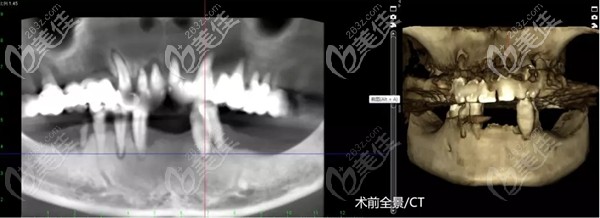

謝大叔術(shù)前口腔CT

術(shù)前先做了口腔CT及數(shù)字化3D導(dǎo)板種植技術(shù)能夠讓醫(yī)生準(zhǔn)確、客觀地判斷出患者的牙槽骨是否適合種植,是否需要進(jìn)行植骨手術(shù),一次就能確定好手術(shù)方案。